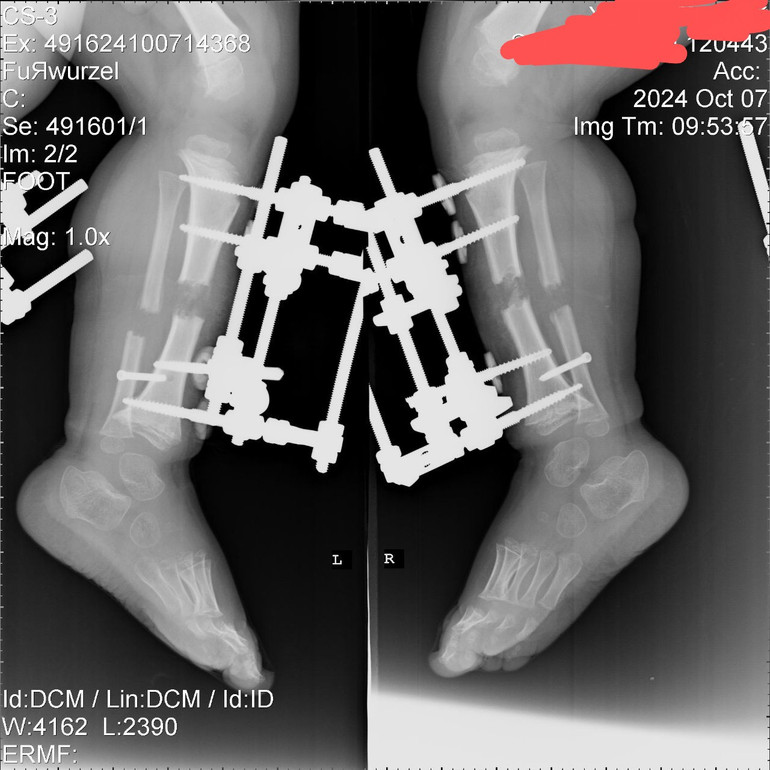

Найпопулярніше доступне лікування – хірургічні втручання з метою продовження кінцівок. Лікарі-ортопеди поетапно встановлюють дитині апарти зовнішньої фіксації (раніше застосовували спицеві апарати Ілізарова) одночасно на дві великогомілкові, стегнові або плечові кістки. Це дає можливість подовжити їх як мінімум на 40%. Механізм апарата передбачає “підкручування” спеціальних деталей, через що й відбувається поступове “розтягнення” кістки.

У середньому на витягування кожної кістки потрібен рік – пацієнту мають встановити апарати, провести лікування (“розкручувати” кістки) та зафіксувати результат (по 1 місяцю на кожен викручений см).

“Кожні 10 днів треба робити рентген, аби побачити щільність нової тканини. Ми ніколи завчасно не знаємо, на скільки вдасться подовжити кістки за один такий цикл“, – пояснює Євген.

Ось так виглядають гомілки під рентгеном. У місці “розриву” утворюється регенерат, який і продовжить кістки / фото з архіву

Якщо “розкручувати” апарат на кістці зашвидко чи забагато, може утворитися дуже крихка кісткова тканина. Це власне, й контролює лікар. Він може тимчасово зупинити або сповільнити подовження.

18 вересня 2024 року лікарі провели першу операцію для Кості з встановлення апаратів зовнішньої фіксації у великогомілкову та малогомілкові кістки на обох ногах. Операція тривала близько 8 годин.

“З 25 вересня 4 рази на день ми крутимо верхні гайки. За добу це подовжує кістку на 1 мм. Нам вдалось “викрутити” 45% від зон росу – 4 см 6 мм“, – розповідає батько хлопчика з карликовістю.

Під час операції хірург розсікає кістку у декількох місцях та встановлює апарат зовнішньої фіксації. Потім поступово (зазвичай на міліметр на добу) кістку “подовжують”, даючи організму змогу нарощувати нову тканину в зоні розрізу.